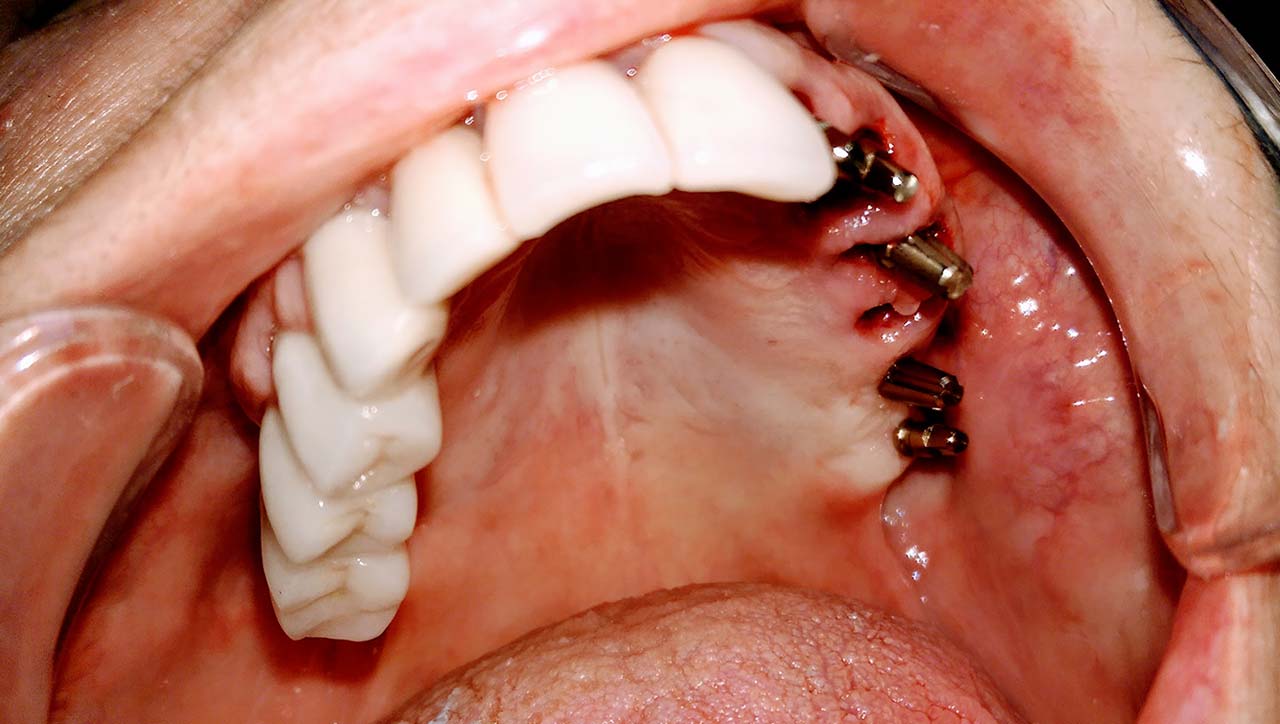

A mozgó, törött fogakon álló hidat a fogakkal együtt eltávolítottuk.

A fogak helyére, és a stratégiailag jó csontállományú hátsó területre azonnal behelyezett implantátumokra 3 nap múlva elkészítettük az esztétikus, azonnal terhelhető ideiglenes hidat.

Esztétikus Implantáció